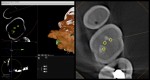

I have always wondered entry into the canal orifice requires precision but even more challenging is to be able to do it through 7-10 mm of dentin.

Any specific bur ? The angles of entry ?

Any slim ultrasonic to smoothen the entry point into dentin and the canal orifice ?

What kind of motions in this access referring to ergonomics ?